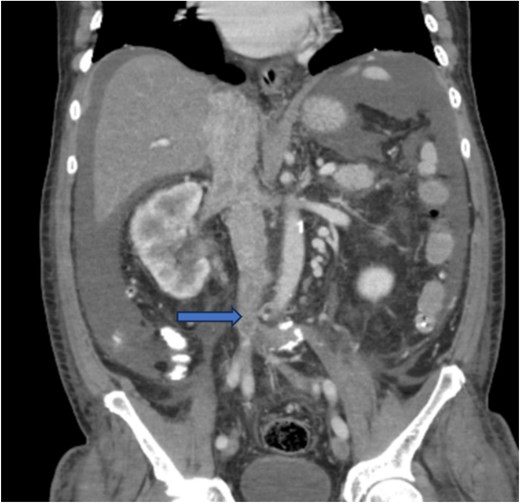

Diagnostic imaging began with a chest X-ray that indicated bilateral pleural effusions. An abdominal ultrasound detected a 4.6 × 4.2 × 4.3 cm echogenic lesion in the right hepatic lobe. Further imaging with a computed tomography (CT) scan of the chest, abdomen, and pelvis revealed a large mass originating from the posterior aspect of the right mid-kidney consistent with RCC (Fig. 1). The mass associated with thrombus extended into the renal sinus and collecting system, traveled along the right renal vein to the inferior vena cava (IVC), and projected into the right atrium (Figs 2 and 3). During hospitalization, bilateral lower extremity pain led to the diagnosis of bilateral deep vein thromboses via duplex venous ultrasound. Echocardiography showed normal left ventricular ejection fraction, impaired diastolic filling, mildly increased ventricular wall thickness, and an echogenic mass extending from the right atrium into the IVC consistent with the tumor thrombus.

CT chest abdomen and pelvis with contrast showing middle portion of right with tumor during venous phase venous phase.

CT chest abdomen and pelvis with contrast showing tumor thrombus is seen within the IVC extending over a long distance from the level of the renal vein cephalad into the right atrium.

CT chest abdomen and pelvis with contrast showing inferior extension to the level of the distal margin of the IVC.